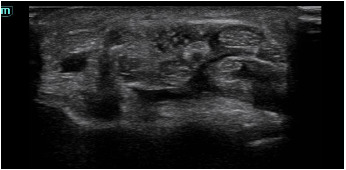

Descripción de los hallazgos ecográficos y las imágenes más relevantes para la resolución del caso

Signos de compresión del nervio mediano: área del nervio mediano 0,11 cc (> 9 patológico) con imagen en reloj de arena en la entrada del túnel del carpo.

Se sigue clínica y ecográficamente a la paciente en consulta. Se comprueba mediante ecografía la liberación del nervio mediano con la segunda intervención, acompañada de la ausencia de sintomatología en la paciente.